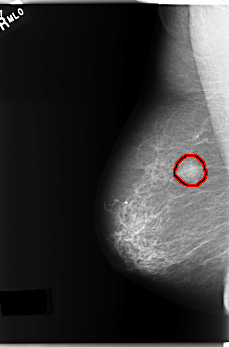

FILE: C_0231_1.RIGHT_MLO.OVERLAY

TOTAL_ABNORMALITIES 1

ABNORMALITY 1

LESION_TYPE MASS SHAPE ROUND MARGINS ILL_DEFINED

ASSESSMENT 5

SUBTLETY 5

PATHOLOGY MALIGNANT

TOTAL_OUTLINES 1

BOUNDARY